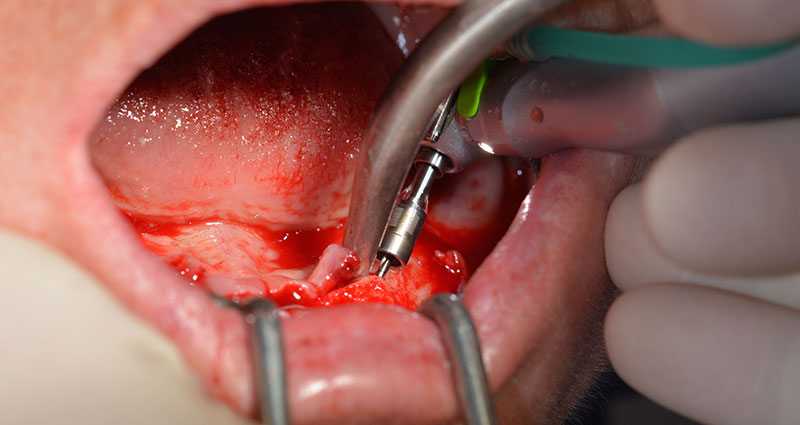

El protocolo quirúrgico de los implantes utilizados (SKY, bredent medical) prescribe una velocidad de 1 200/rpm para las perforaciones piloto (figs. 7-9).

Este valor se corresponde con la posición siguiente del ajuste predefinido en Implantmed. Aquí se aprecia la inclinación de aproximadamente 45 grados del contra-ángulo de W&H hacia medio caudal en la región de la pieza 45 para preservar el nervus mentalis. El foramen mentale sirve como orientación anatómica para todas las perforaciones en esta zona. Las perforaciones siguientes se realizaron con una velocidad reducida de 300/rpm (figs. 10 y 11).